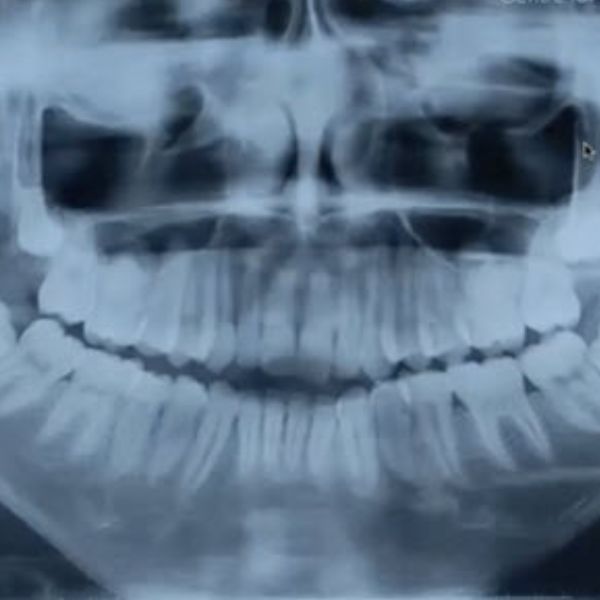

The goals of pediatric Temporomandibular Joint (TMJ) reconstruction are to maintain pain-free mouth opening and prevent re-ankylosis or heterotopic bone formation. We are doing these techniques in small children, but small children will grow. This means adopting a technique that will grow with the children, that would limit asymmetry. There are considerations to differing techniques to TMJ reconstruction in children.

Obviously, children who have undergone TMJ surgery at a very young age will have a small mandible. This decreases the airway space and predisposes these patients to obstructive sleep apnea later on, so we also need to increase the airway space.

Let us first look at what happens when you do no reconstruction in cases where the children are operated on, or diseases of the temporomandibular joint ankylosis, let's say temporomandibular joint. If we consider a case of bilateral ankylosis, one year postoperative, the patient will probably be doing fine, and function is restored. Even three or ten years on, we might say the same.

But what has really happened is that while the mouth opening is adequate, no catch-up growth has happened, even when the functional matrix is restored as per Moss’s theory. Functional treatment has happened, but the growth has not, so aesthetics is compromised.

Another reason why reconstruction should be done is osteoarthrotomy, or a lack of growth in the condyle, if you don’t reconstruct them. We have shown that in two of our publications, where there is a loss of vertical height and the mandible rotated backwards. This pushes the tongue into a more posterior position, causing obstructive sleep apnea. These cases are detailed in the January 2021 and December 2021 Journal of Oral Maxillofacial Surgery.